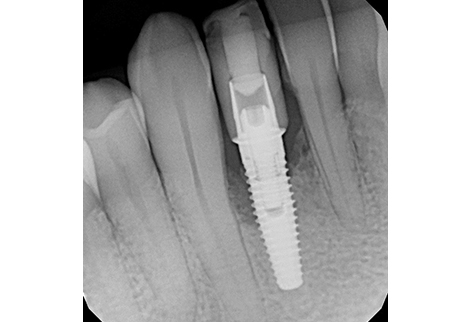

Clinical examination revealed inflamed peri-implant soft tissue, probing depths of 6–8 mm circumferentially, and mild suppuration. No mobility was noted, but the buccal tissue appeared slightly recessed with grey shadowing of the gingival marginal tissues. A periapical radiograph was obtained and showed significant vertical bone loss around the implant extending apically, with crater-like defects on all aspects.

At 4 months post-grafting, a CBCT scan demonstrated sufficient bone volume and density to support a new implant at site #42. A 3.5 x 10 mm narrow-diameter Nobel Biocare TiUltra CC implant was placed at 25 Ncm torque, with ISQ testing measuring 68 and a 3.6 x 3 mm healing abutment inserted at 15 Ncm torque. After 4 months of osseointegration, the implant was restored with a screw-retained zirconia crown, using on-brand Nobel Biocare prosthetic components.

At the 1-year follow-up, the implant was functional with healthy surrounding tissues and no signs of inflammation. The implant–bone crestal bone level was maintained due to improved prosthetic design: good emergence profile, short well-positioned contact areas, and screw-retained prosthetic with proper contours.